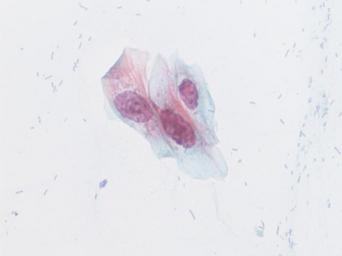

Keywords: lesión intraepitelial escamosa de bajo grado lesiónintraepitelialescamosadebajogrado citología de cuello uterino citologíadecuellouterino citología exfoliativa ginecológica citologíaexfoliativaginecológica citología de cribado citologíadecribado citología anatomía patológica anatomíapatológica bethesda 2001 bethesda2001 osuna cérvix uterino cérvixuterino hpv españa screening lsil enfermedades de transmisión sexual enfermedadesdetransmisiónsexual imágenes de citología ginecológica imágenesdecitologíaginecológica papanicolaou test de papanicolaou testdepapanicolaou tinción de papanicolaou tincióndepapanicolaou white background Células con núcleo y citoplasma aumentado de tamaño, núcleos irregulares, como plumosos, tendencia al color naranja de muchas células, halos en algunos casos, núcleos dobles en otros, algunos núcleos hipercromáticos. Células con núcleo y citoplasma aumentado de tamaño, núcleos irregulares, como plumosos, tendencia al color naranja de muchas células, halos en algunos casos, núcleos dobles en otros, algunos núcleos hipercromáticos.